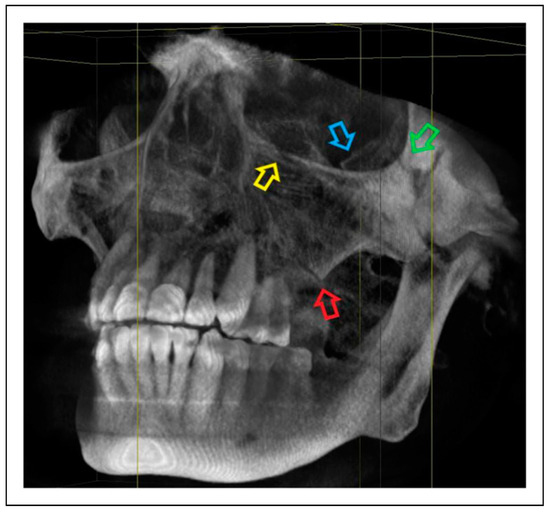

- Zygomaticomaxillary suture (ZM)

- Infraorbital rim (IOR)

- Zygomaticofrontal suture (ZF)

- Zygomaticosphenoidal suture (ZS)—the anterolateral orbital floor

- Zygomaticotemporal suture (ZT)